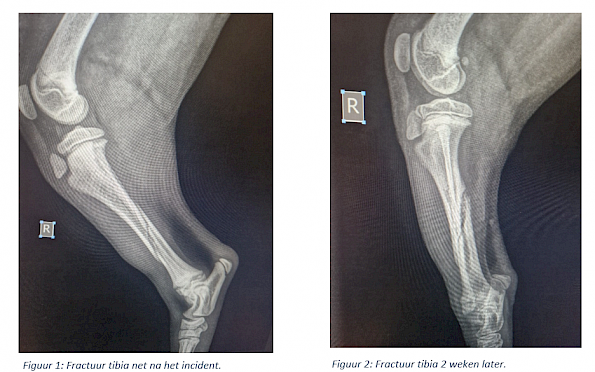

Met deze pup is het allemaal goed afgelopen. Op de onderstaande foto (figuur 1) is de breuk van de rechterachterpoot te zien. Na 2 weken zagen we een mooie callus vorming (figuur 2). Dit betekent dat de breuk netjes aan het genezen was. Na 4 weken was de breuk voldoende hersteld en kon de spalk verwijderd worden.